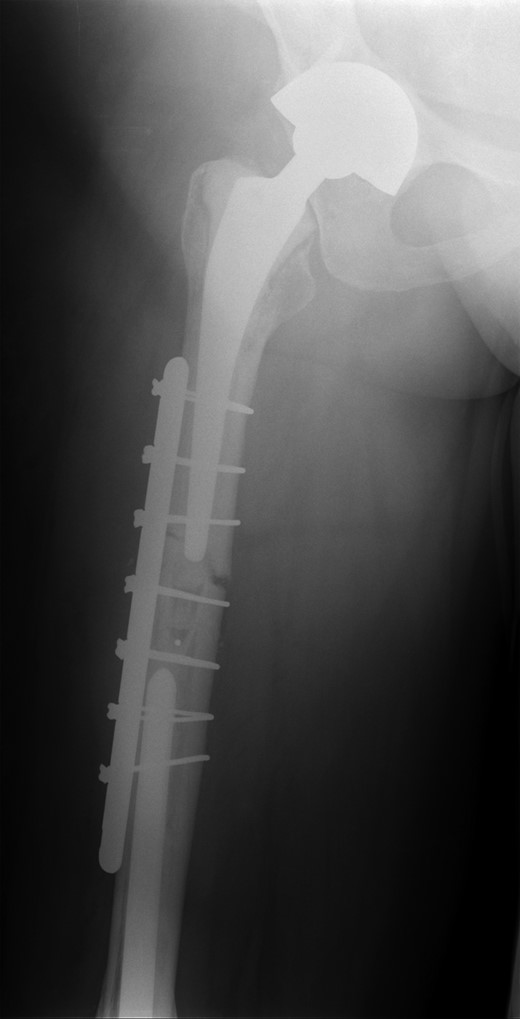

She subsequently sustained a periprosthetic fracture at the distal tip of her right total hip replacement (Fig. 1). An initial attempt was made to manage this fracture with a plate and Dall-Miles cables (Fig. 2); however, the fracture did not unite. The patient went on to have a custom-made cement-linked internal proximal femoral replacement, which had a hollow cylindrical design to accept the stem of the existing well-fixed distal femoral component (Figs 3 and 4). This linked prosthesis effectively converted her separate prostheses to a total femoral replacement, sparing her distal femoral replacement from revision. She had no problems postoperatively and recovered well from her surgery.

Periprosthetic fracture distal tip of right total hip replacement.